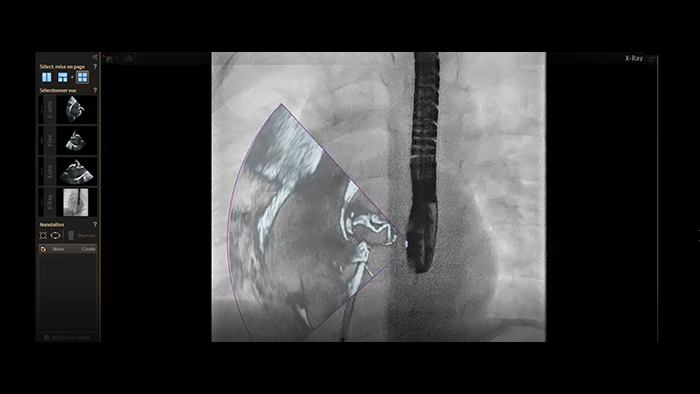

ASD closure with EchoNavigator live fusion